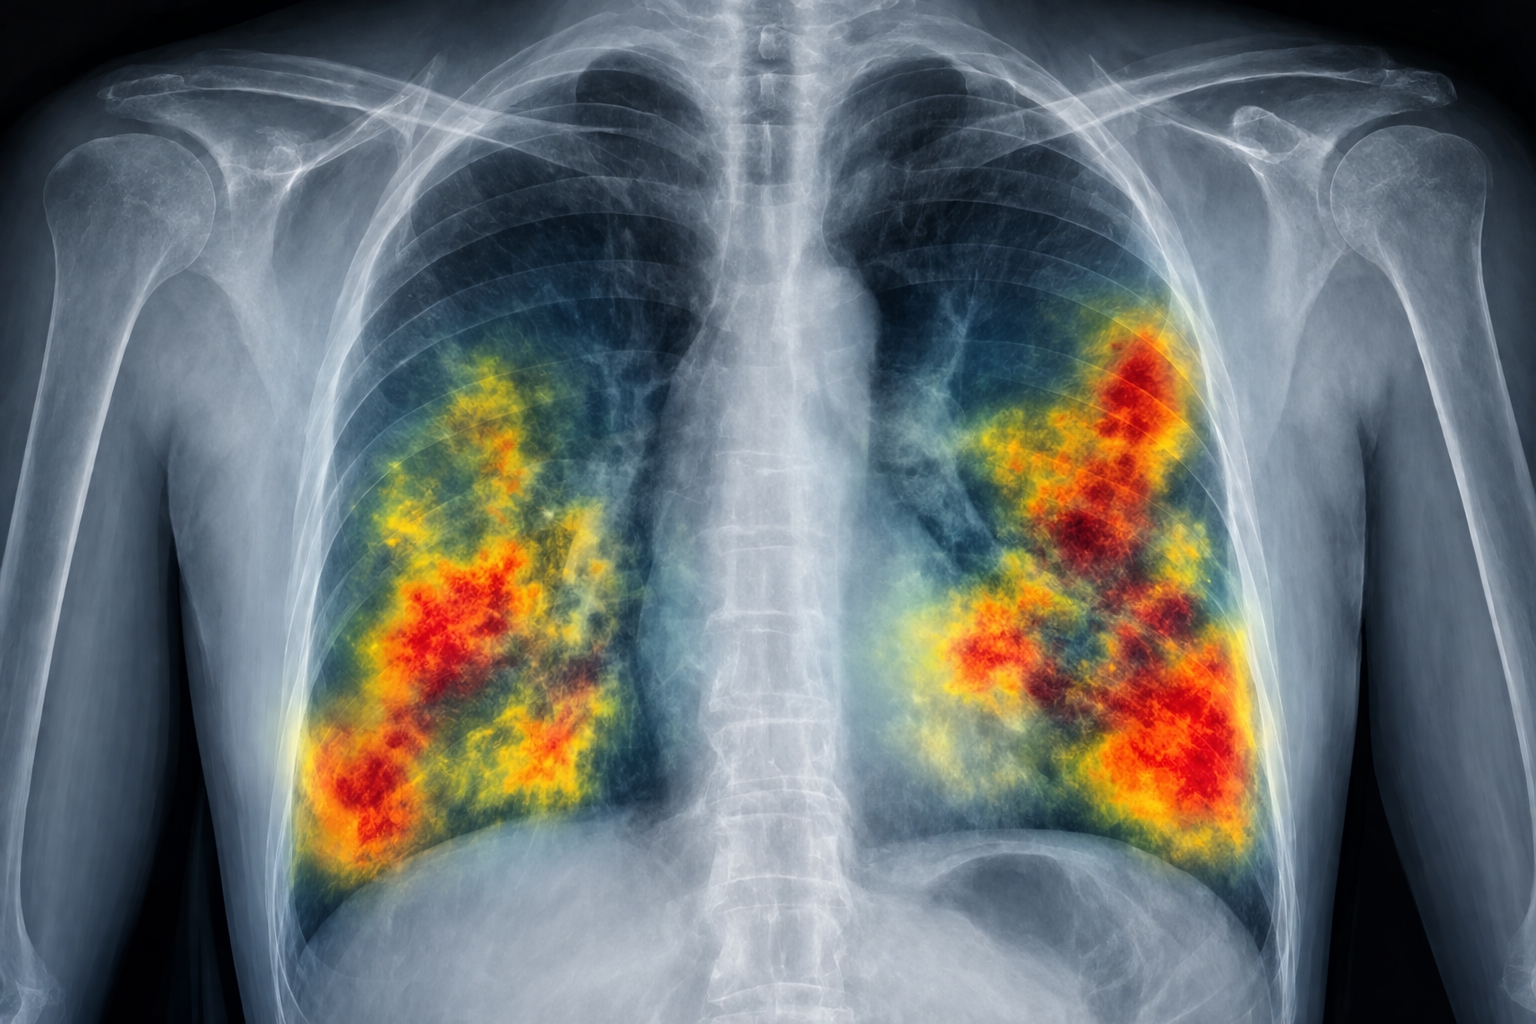

The platform applies advanced computer vision and machine learning techniques to identify patterns that may be difficult to detect through manual analysis alone. By highlighting areas of interest and providing structured insights, it assists specialists in making more informed decisions.